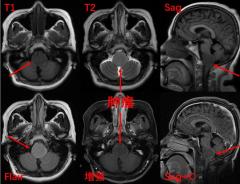

早高峰车祸重伤 西安国际医学中心医院多学科接力上演生死时速